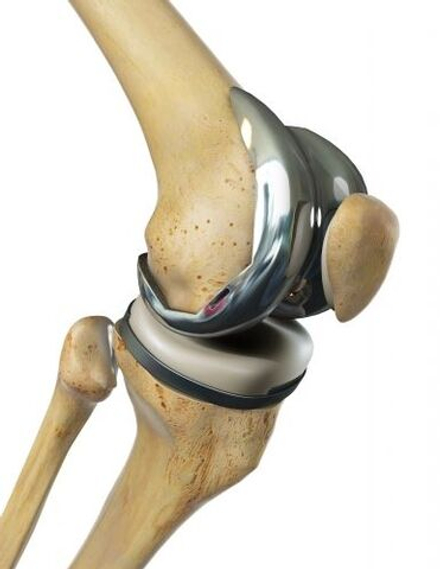

Эндопротезирование коленного сустава

Эндопротезирование — это открытая операция, при которой производится замена поврежденного коленного сустава на современный искусственный имплант.

Современные эндопротезы

Современные типы эндопротезов учитывают сложную биомеханику коленного сустава и максимально точно воспроизводят естественные движения.

Здоровый коленный сустав стабилизируется связками. В зависимости от клинической ситуации:

· некоторые импланты позволяют сохранить собственные связки пациента

· другие полностью берут на себя их функцию

Это обеспечивает стабильность, физиологичность движений и долговечность результата.

Преимущества эндопротезирования:

· устранение хронической боли

· восстановление функции сустава

· возвращение к активной жизни

· долгосрочный результат